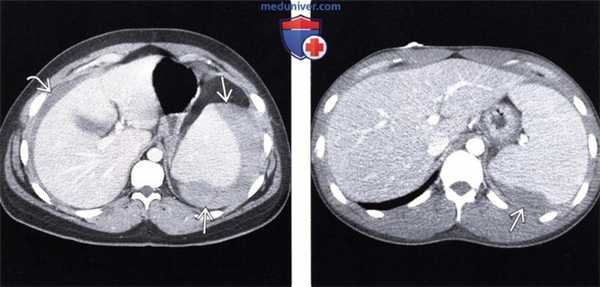

(Слева) На изображении в коро-нальной плоскости при КТ с контрастным усилением определяется диффузное опухолевидное утолщение стенки и расширение тонкого кишечника в левом нижнем квадранте, видно также контрастное вещество в просвете кишки. Чуть выше обратите внимание на выраженную лим фаденопатию. Эти изменения обусловлены подтвержденной биопсией СПИД-детерминированной неходжкинской лимфомой.

(Справа) На аксиальном срезе при КТ с контрастом определяется выраженная мезентериальная лимфаденопатия, обусловленная СПИД-детерминированной неходжкинской лимфомой.